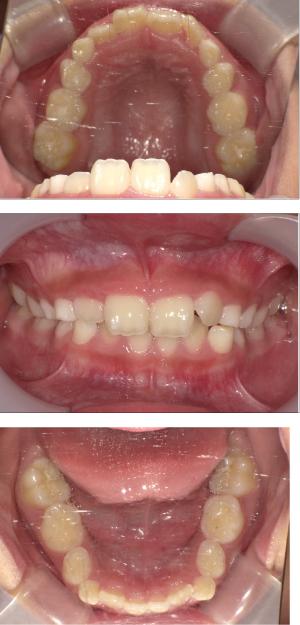

治療開始年齢

6.7歳以降~10歳前後まで

(歯の生え変わりスピードによって個人差はございます)

- 年齢制限がある。第二乳臼歯が抜けてしまうと治療が困難。

矯正治療は大人になって始めるよりも子どもの頃から始めた方が確実に良い結果をもたらします。成長が盛んな子供の時期に、顎や顔の成長を利用しながら治療ができる大きなメリットがあるからです。当院では、非抜歯矯正を推奨しておりバイオブロック矯正を取り入れています。

バイオブロック矯正の考え方は歯並びが悪くなる原因にアプローチする治療法になります。

舌の位置や口呼吸から乱れてしまった下顎の後退を正し、顎顔面が本来あるべき位置へと誘導させていく治療です。